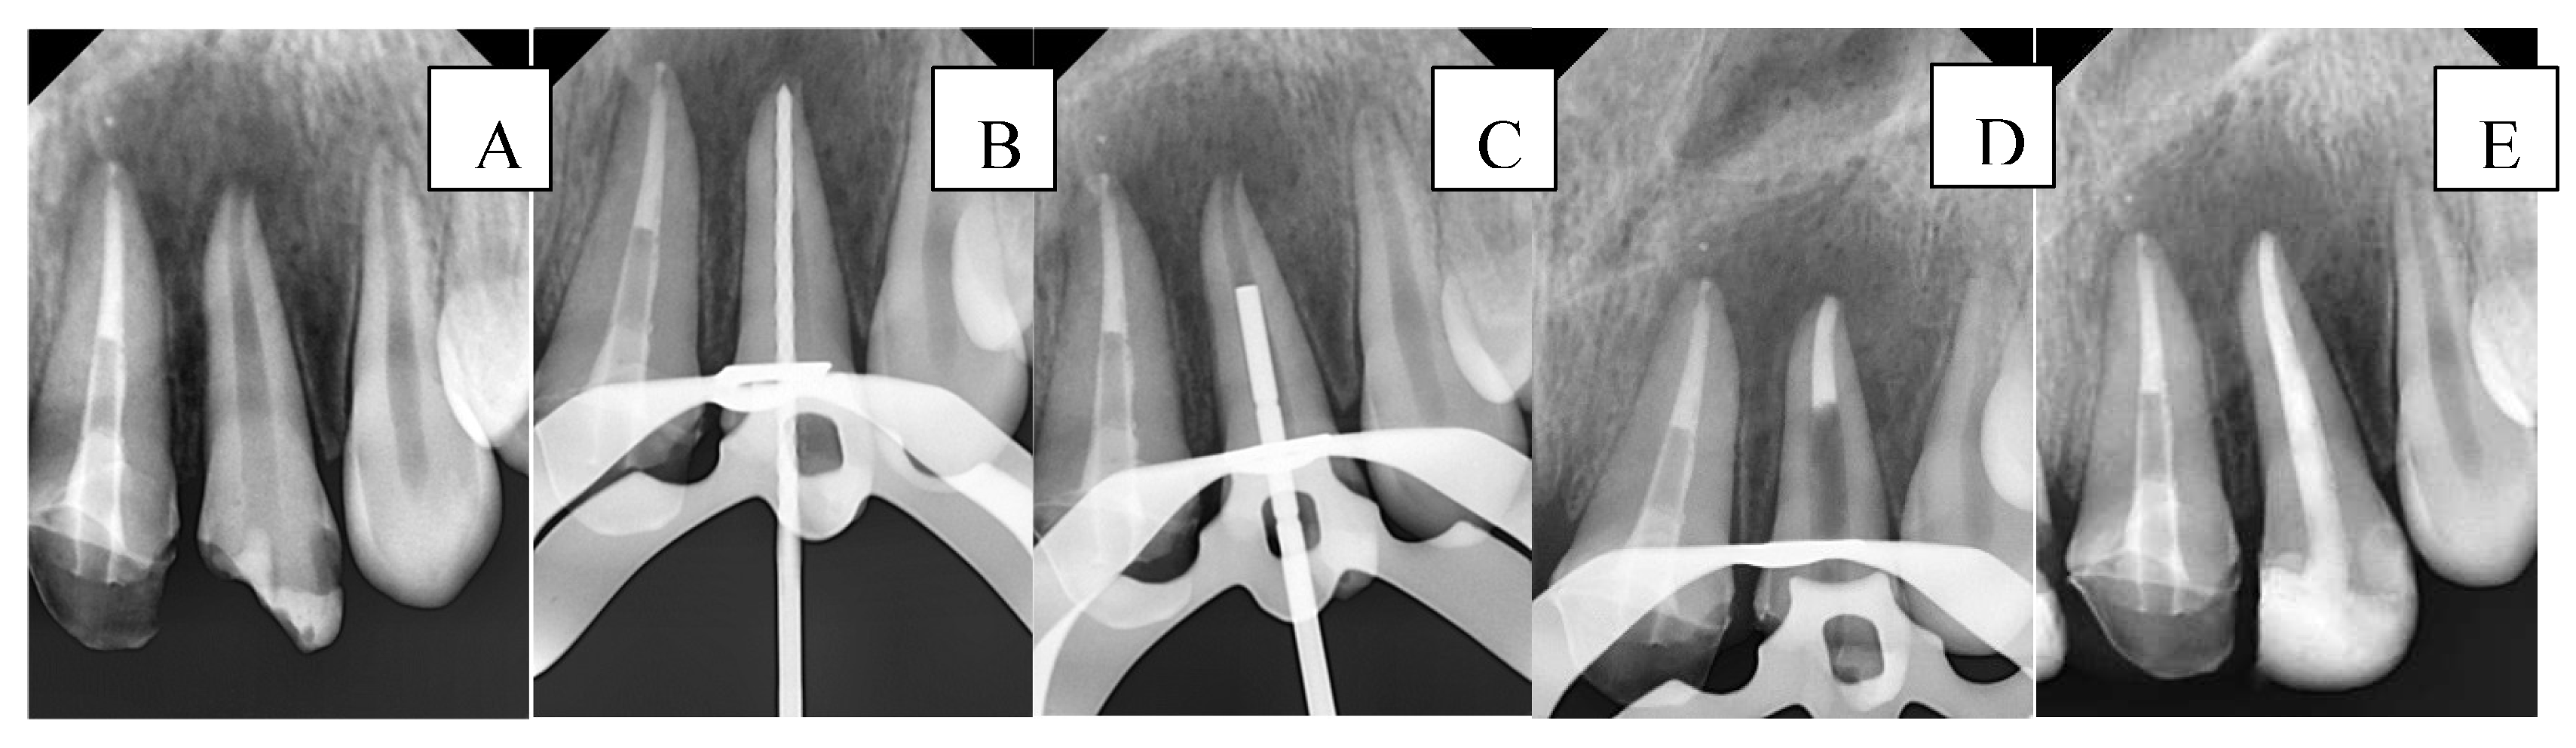

A radiograph was first taken with the hand plugger to ensure that it reached 4 mm short of the radiographic apex, as specified by the WL. The BioCeramic Putty (BP) (TotalFill® BC RRM™, FKG Dentaire, Le Crêt-du-Locle, Switzerland) was applied to the apical 4 mm of the canal using a modified cannula [35], with placement adapted using a hand plugger and confirmed radiographically. Any BE was recorded at this stage in the DPF. The incisors were then temporized with a cotton pellet and glass ionomer filling. The following day, after isolation and removal of the temporary filling and cotton pellet, the remaining canal space was obturated with gutta-percha and BioCeramic Sealer (BS) (TotalFill® BC Sealer™, FKG Dentaire, Le Crêt-du-Locle, Switzerland) using the cold lateral condensation technique. A periapical radiograph confirmed that the canal was obturated without voids or gaps. Figure 2 illustrates the steps of the procedure in the BPAP group.

Figure 2. Sequential steps of the procedure in the BPAP group: A- Preoperative periapical radiograph, B- Working length radiograph, C- Plugger fit, D- Apical plug formation, E- Postoperative radiograph.